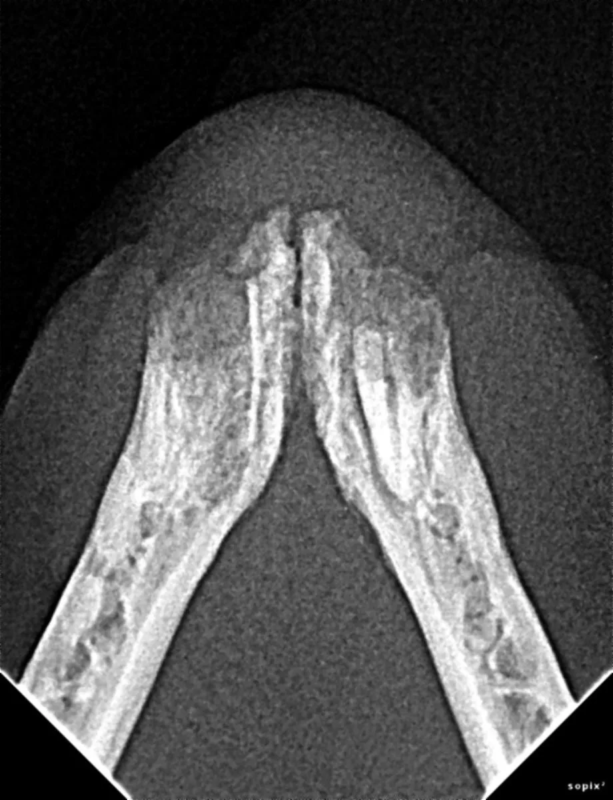

Cone Beam Computed Tomography

The Center now provides advanced imaging via cone beam CT. Cone beam CT is excellent for visualization of bony structures of the skull, nasal cavity, teeth, and ears. Cone beam CT is especially helpful for diagnosing dental disease and evaluation of jaw fractures. It can also be useful for evaluating the sinuses and tympanic bulla. Cone beam CT can be used in conjunction with nasal biopsy and culture to evaluate nasal discharge whether chronic or acute.

Repair of Maxillofacial Fracture

Pets can be involved in trauma that can cause fractures to their head, teeth, and jaw bones. Correctly repairing these fractures is extremely important for your pet to have normal function of their mouth. If a jaw fracture is allowed to heal in an abnormal position, your pet may have great difficulty chewing and can be in significant pain. Many fractures can be successfully treated with minimally invasive oral procedures, but more complicated cases may require bone plating techniques. The Center offers cone beam CT imaging which provides extremely detailed images of the bones of the head and skull. Advanced imaging with CBCT facilitates selection of the best surgical technique to get your pet back to eating and comfort as soon as possible.